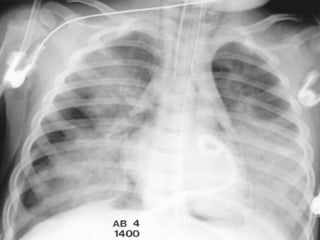

Adult Respiratory Distress Syndrome

Non-cardiogenic pulmonary edema

Distinguishing characteristics:

Normal size heart

No pleural effusion